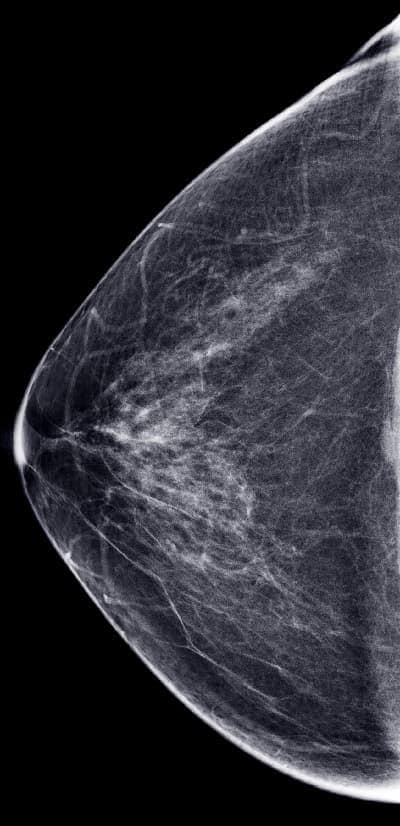

An example of a normal mammogram. Each woman’s mammogram may look a little different because all breasts are a little different.

A mammogram is an X-ray picture of the breast. Doctors use a mammogram to look for early signs of breast cancer. Regular mammograms can find breast cancer early, sometimes up to three years before it can be felt.